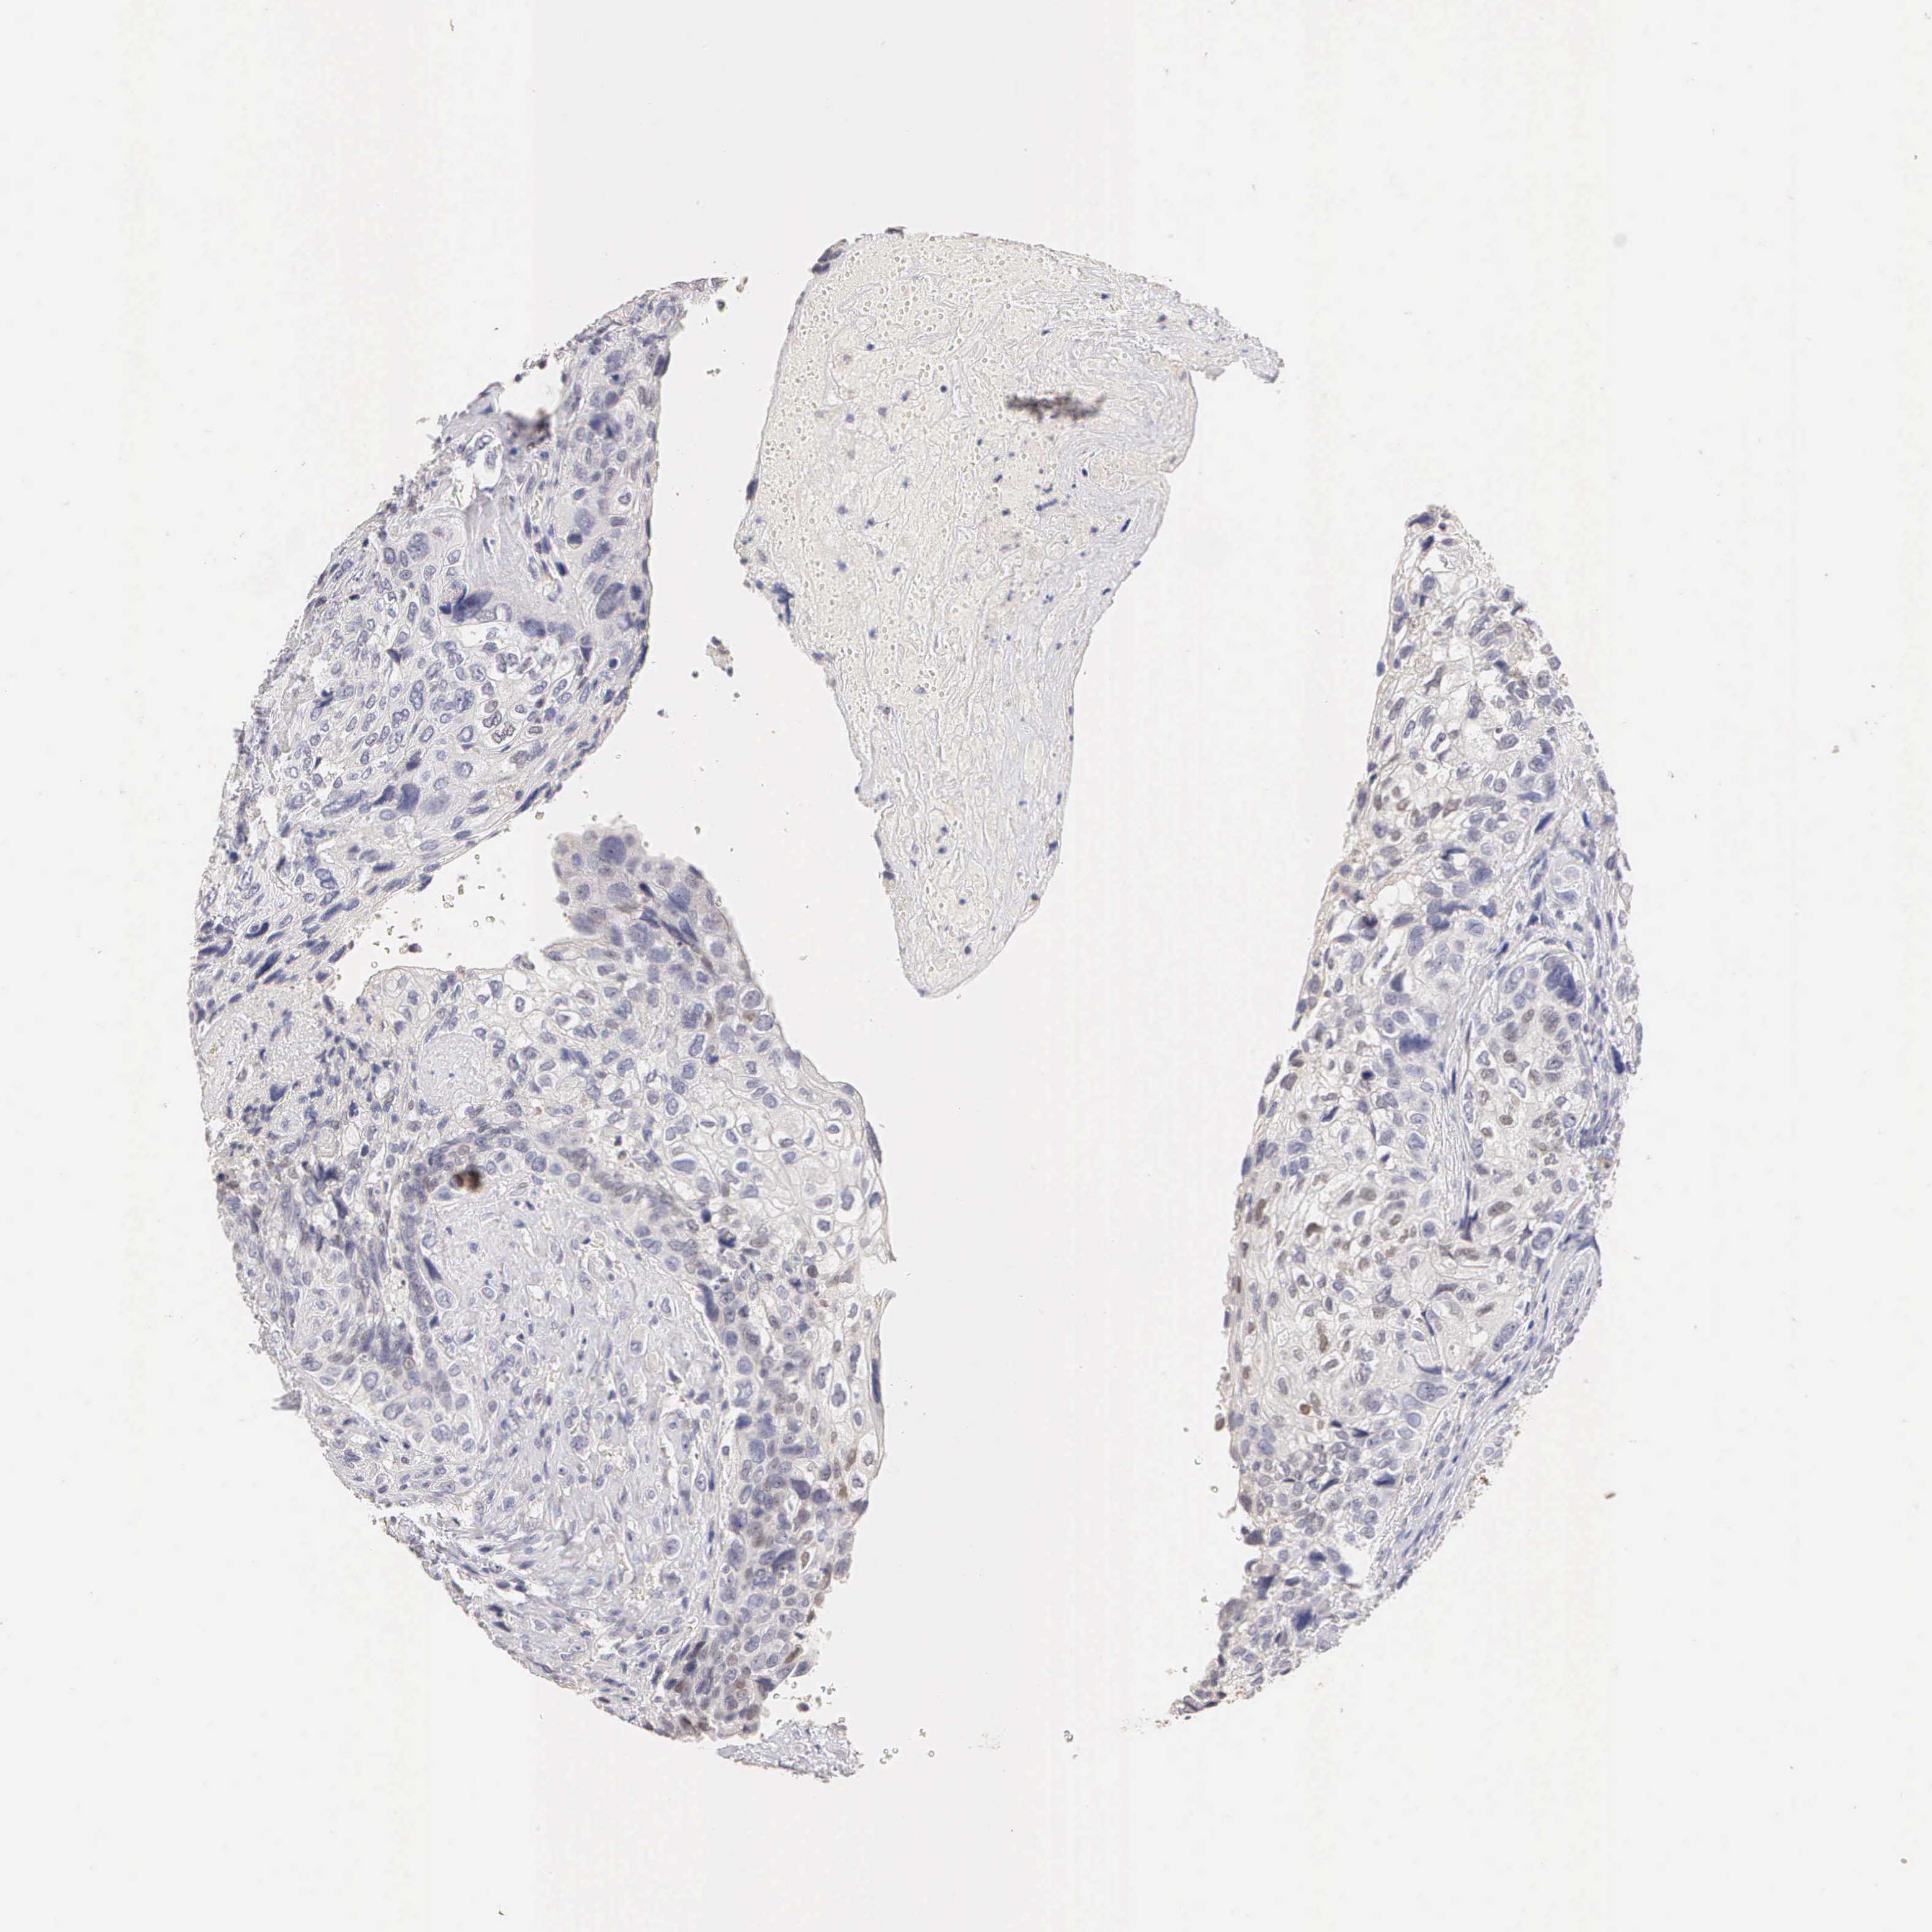

Breast cancer

Human cancer